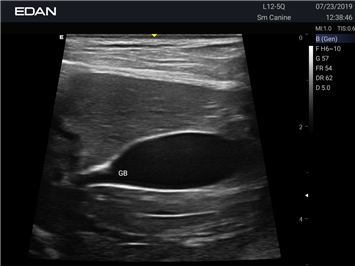

Ветеринарный ультразвук одним нажатием. Система Acclarix AX2 VET разработана с целью обеспечить бескомпромиссную производительность по доступной цене. Наличие уникальных двойных аккумуляторов в легком корпусе массой 4,5 кг из магниевого сплава позволяет системе Acclarix AX2 VET удовлетворять все потребности ветеринарных исследований, сохранив низкую стоимость.

EDAN Acclarix AX2 VET представляет собой специализированную ветеринарную ультразвуковую систему, сочетающую высокую производительность с доступной ценой. Благодаря продуманной конструкции и передовым технологиям, система обеспечивает качественную диагностику животных различных видов.

• Высокое разрешение для детальной диагностики

• Улучшенная визуализация глубоко расположенных органов

• Предустановленные протоколы для различных видов животных